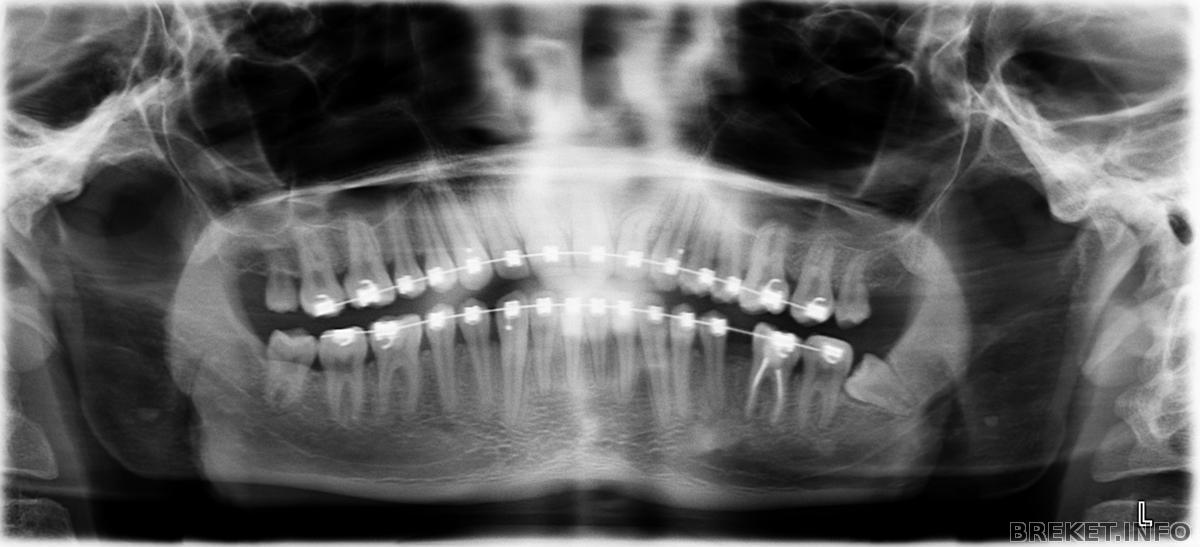

Зуб находится в десне так что не знаю как его будут вытаскивать. Боюсь он сможет задеть рядом стоящий зуб. Хотя хирург говорил что легко сможет.

Снимок был сделан летом. И ситуация немного изменилась, промежуток немного затянулся.

Не знаю нужно ли делать еще снимок.